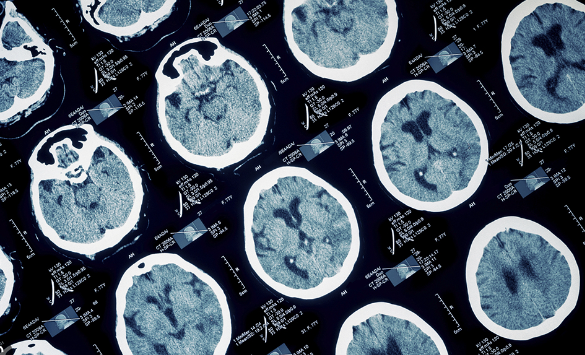

파킨슨병은 중추신경계 질환 중 하나로, 신경세포 손상으로 인해 동작을 조절하는 뇌 부위에서 생기는 문제로 인해 나타나는 질환입니다.

파킨슨병은 주로 신경과 의사에 의해 진단됩니다. 의사는 증상을 보고 환자의 진료기록, 유전적 위험요인 등을 고려하여 진단을 내립니다.